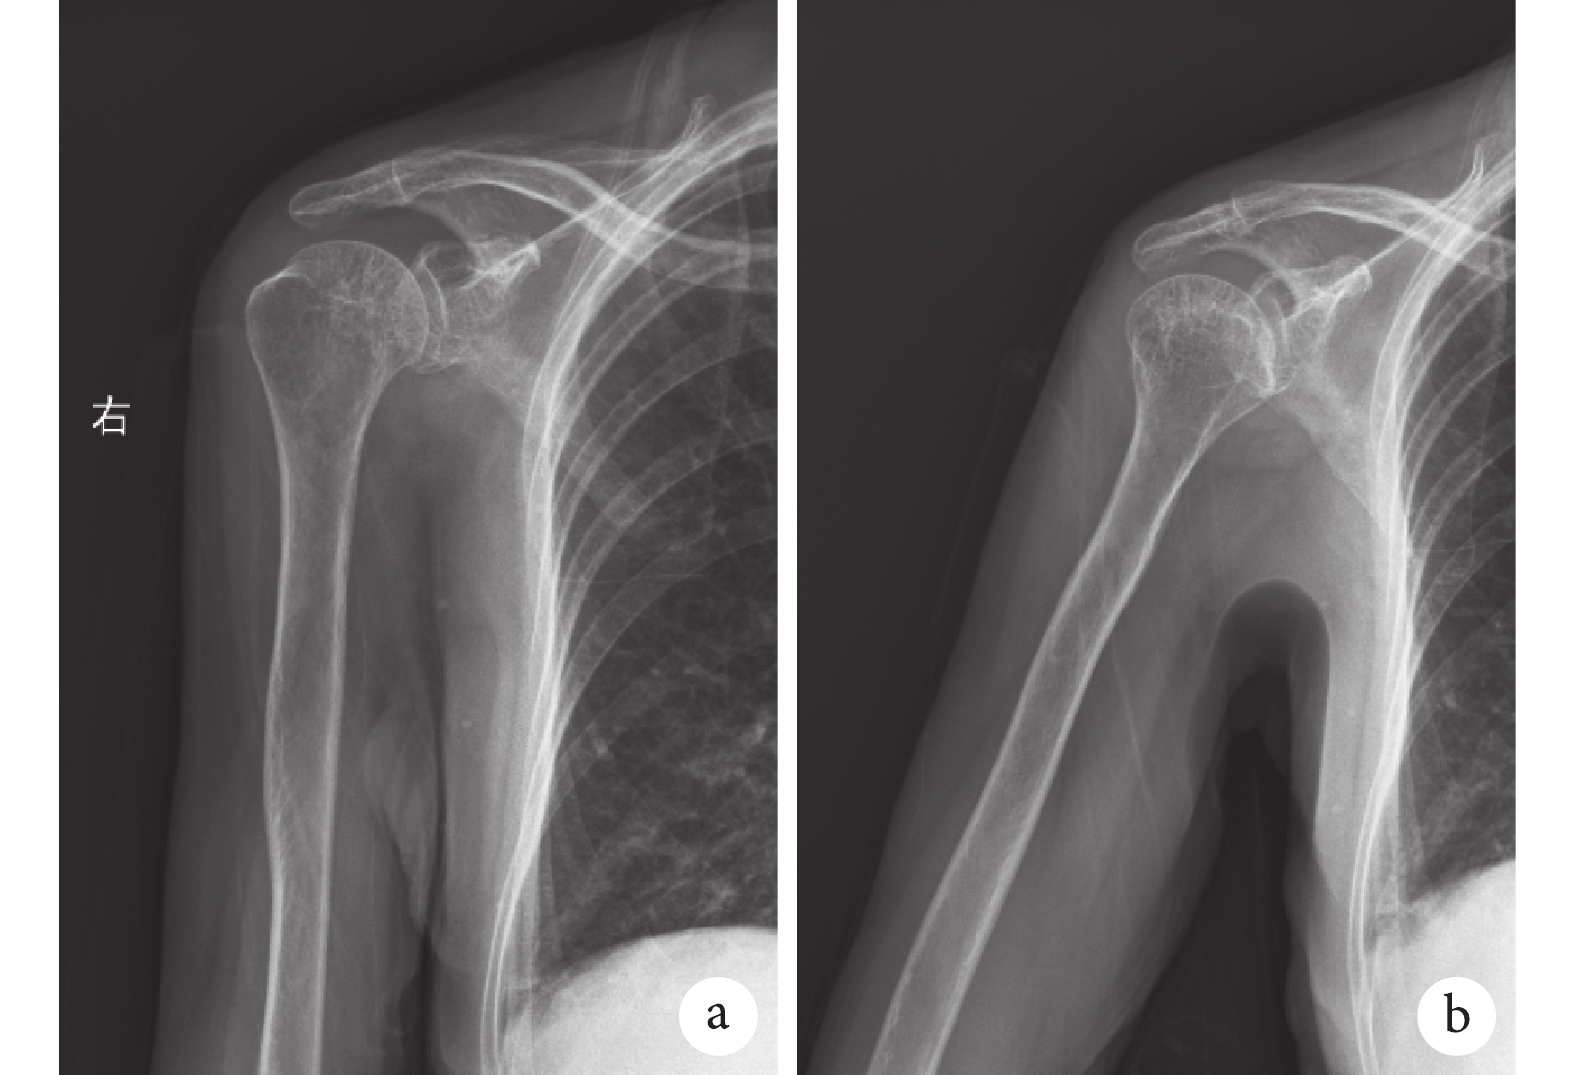

輔助檢查:肝腎功能、電解質、凝血常規無明顯異常。血常規:白細胞計數 5.99×109/L,紅細胞計數 3.70×1012/L,血紅蛋白 119 g/L,血小板計數 149×109/L,血細胞比容 35.7%,中性粒細胞百分數 57.6%,中性粒細胞絕對值 3.45×109/L。C 反應蛋白 5 mg/L。紅細胞沉降率 13 mm/h。心臟超聲:左心房增大。右上肢血管超聲:右側尺動脈內膜增厚不光滑伴散在鈣點及鈣斑形成,部分段管腔狹窄、閉塞伴側支血管形成。右肩關節“Y”位 X 線片及肩關節正位 X 線片提示:肩峰下方可見高密度云霧狀鈣化影(圖 2a、2b);右肩關節 CT 提示:肩峰下與肱骨大結節間見團塊狀高密度影(圖 2c、2d);右肩關節 MRI 提示:肩峰下低信號影,肩袖無明顯撕裂(圖 2e、2f)。

a、b. 分別為“Y 位”和正位 X 線片,均提示肩峰下與肱骨大結節間云霧狀鈣化影(白箭);c、d. 術前肩關節 CT 像,示肩峰下與肱骨大結節間高密度鈣化影(白箭);e、f. 術前肩關節 MRI 像,e 示肩峰下低信號影(白箭),f 示肩袖連續性存在、無明顯撕裂(白箭)